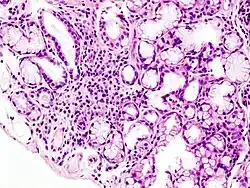

Transverse section of Villus showing goblet cells

The villi are covered with goblet cells. About a quarter to a half of the villi cells are mucous producing.